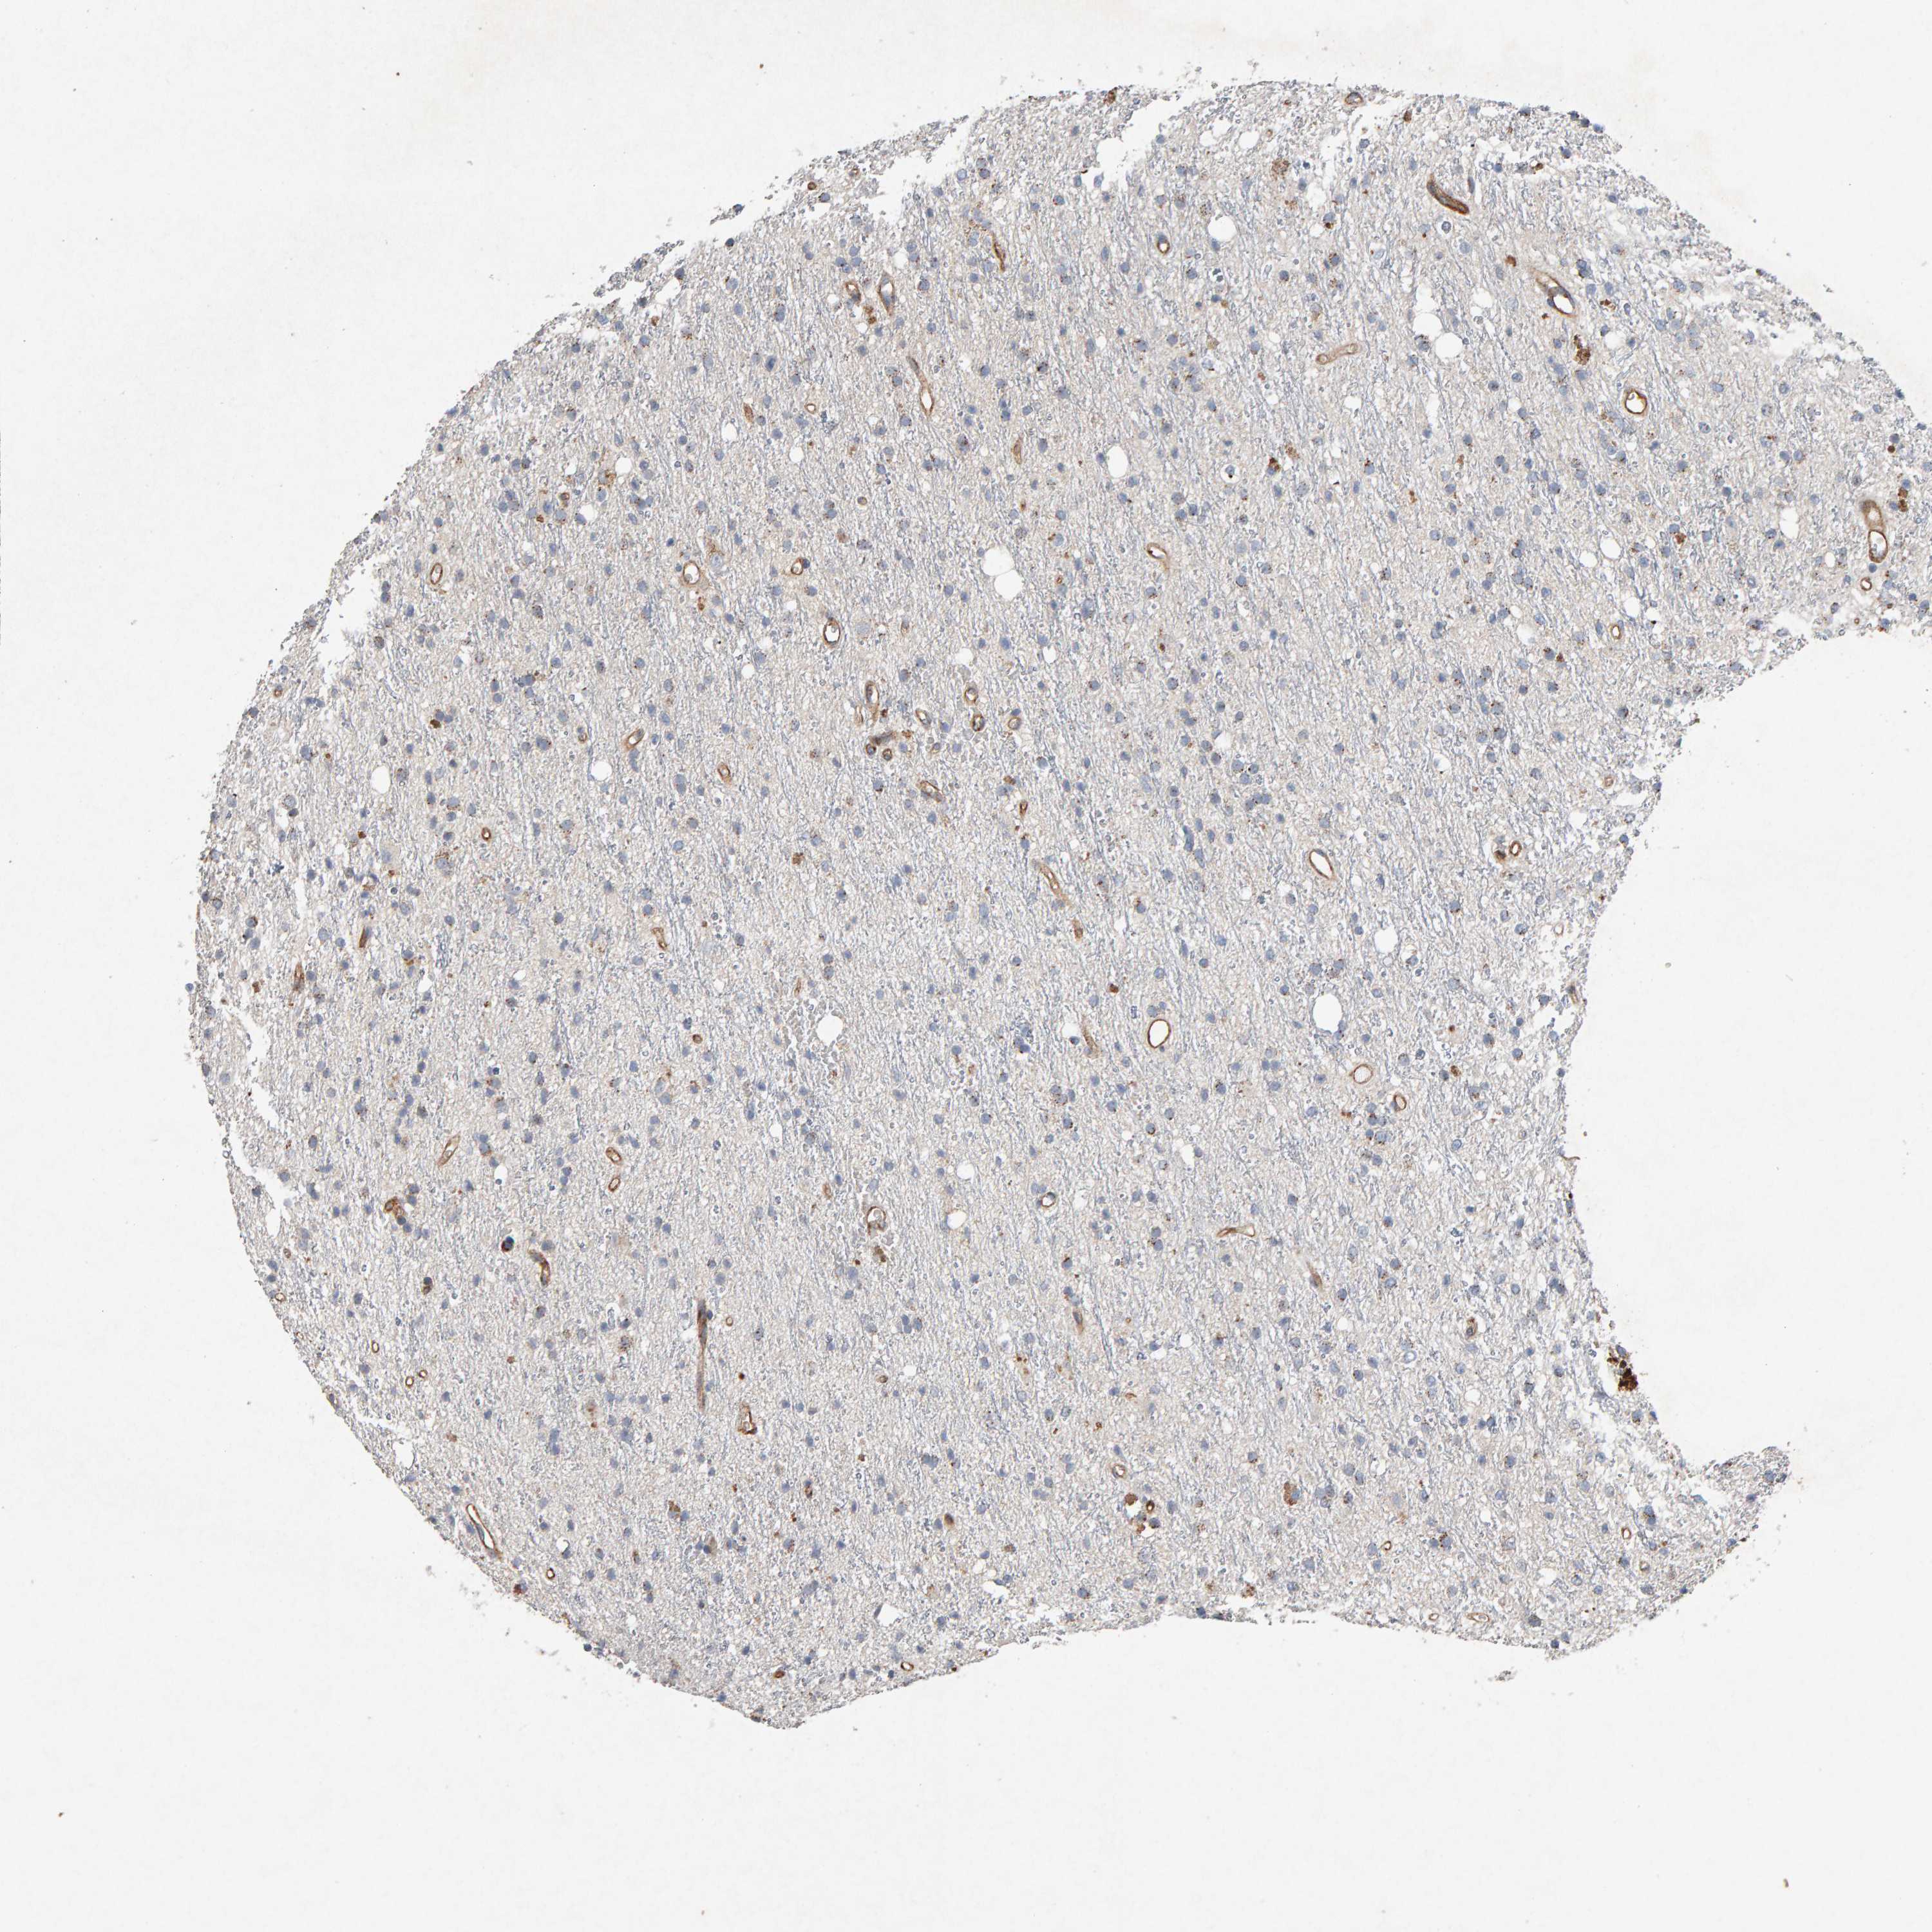

GLIOMA - Protein expressioni

A mouse-over function shows sample information and annotation data. Click on an image to view it in a full screen mode. Samples can be filtered based on level of antibody staining by selecting one or several of the following categories: high, medium, low and not detected. The assay and annotation is described here.

Note that samples used for immunohistochemistry by the Human Protein Atlas do not correspond to samples in the TCGA dataset.

Antibody stainingi

Antibody staining in the annotated cell types in the current human tissue is reported as not detected, low, medium, or high, based on conventional immunohistochemistry profiling in selected tissues. This score is based on the combination of the staining intensity and fraction of stained cells.

Each image is clickable and will lead to virtual microscopy that enables deeper exploration of all samples and also displays staining intensity scores, fraction scores and subcellular localization as well as patient and tissue information for each sample.

Antibody CAB022442

Antibody CAB022443

Staining

High

Medium

Low

Not detected

Intensity

Strong

Moderate

Weak

Negative

Quantity

>75%

75%-25%

<25%

None

Location

Nuclear

Cytoplasmic/membranous

Cytoplasmic/membranous,nuclear

Glioma, malignant, High grade

Glioma, malignant, Low grade